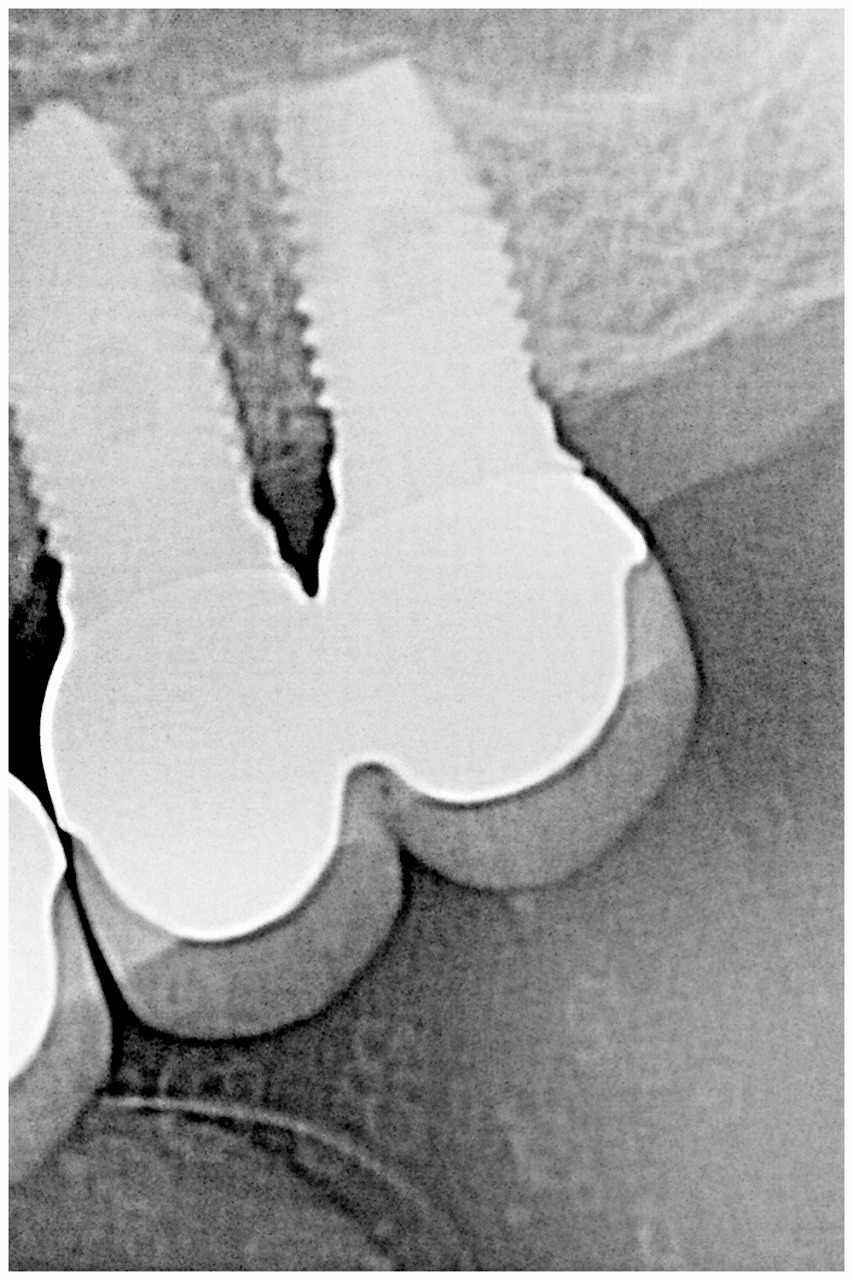

デンタルレントゲンになります

綺麗に持ち上がりました